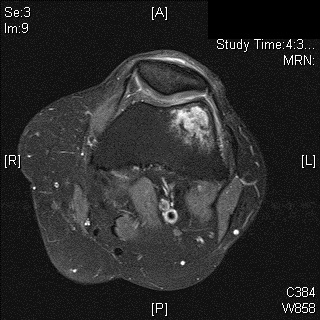

MRI

• MR Imaging, demonstrates intermediate to hypointense signal on T1-weighted images (Fig. 4 & 5) and hyperintensity on T2-weighted images (Fig. 6 & 7).

• Most cases show an extraosseous mass and cortical disruption on MRI.

Fig. 6

Fig. 7

Fig. 6 & 7: MR Imaging. Axial (Fig. 6) and Coronal (Fig. 7) T2 fat saturated image demonstrating T2 hyperintense lesion within the lateral supracondylar femur with a small amount of surrounding bone marrow edema.